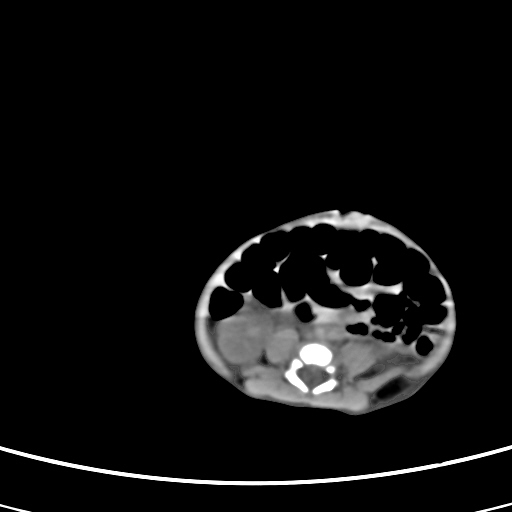

患儿,男性,出生后2天,在胎儿时b超已发现病变,患儿一般情况可。因病变部位偏向于右侧肾上腺区,目前考虑为神经母细胞瘤,不知各位能否支持。

病灶内未见明显脂肪密度。

反对定位在右肾上腺区的说法,那么神经母细胞瘤也可以暂时不予考虑。请看下图:

下面这幅图中,似乎可以见到肿瘤的薄包膜,其后与右肾之间的又是什么东西呢?这关系到肿瘤的定位、定性。我考虑病灶是位于肝十二指肠韧带内的畸胎瘤可能性比较大。请各位老师仔细看一下:

病灶巨大,位于右侧肾上腺区,与周围组织分界欠清,内见不规则钙化影,无明显脂肪组织,首先考虑神经母细胞瘤,但畸胎瘤不能排除。

手术结果为畸胎瘤